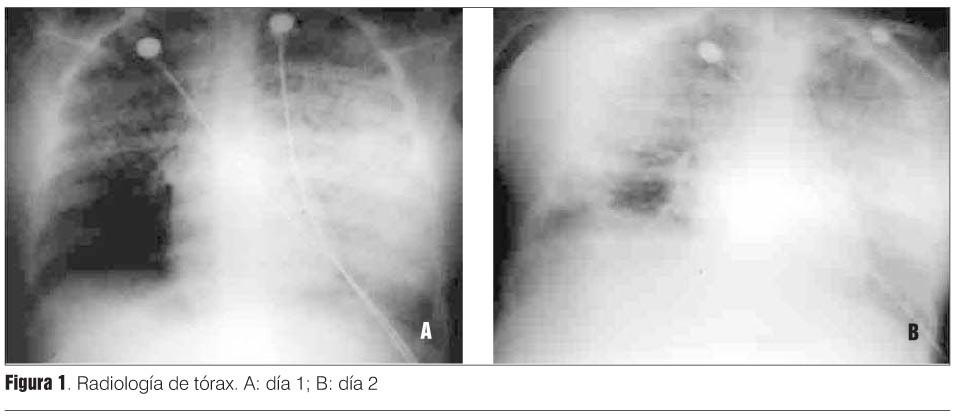

Radiografía de tórax: patrón de consolidación parenquimatosa bilateral (figura 1).

Radiografía de tórax: progresión radiológica (figura 1B).